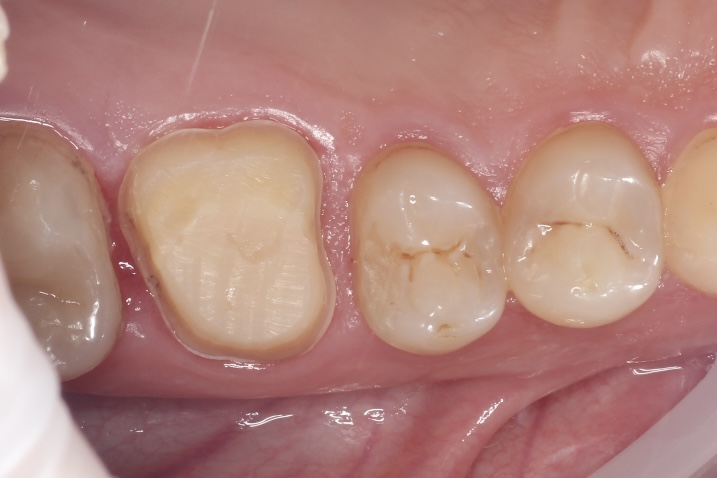

Наши работы